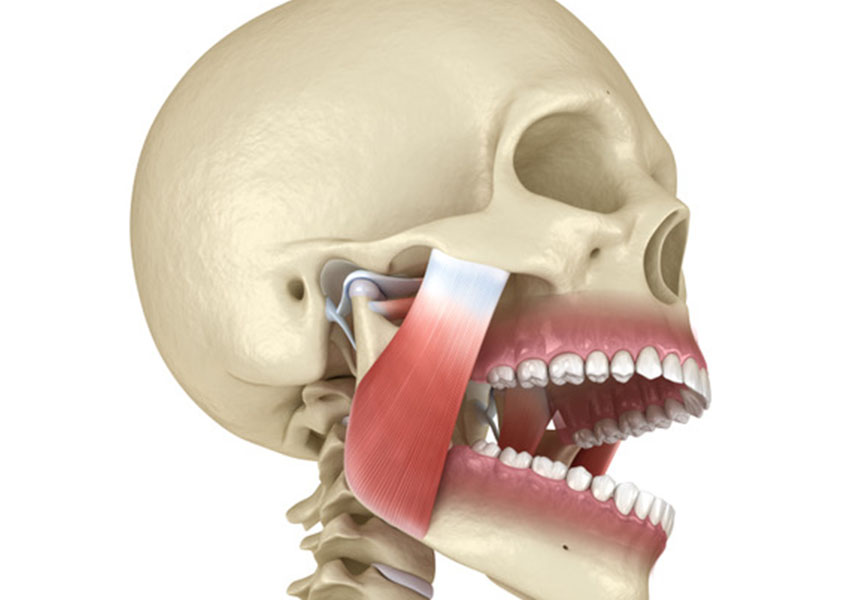

Schienentherapie

Mit unseren Schienentherapien können wir nächtlichem Schnarchen, Substanzverlust der Zähne durch Knirschen sowie Fehlstellungen des Kiefers und daraus resultierenden Verspannungen im Kopf- und Nackenbereich entgegenwirken. Sprechen sie uns an, wir beraten Sie gerne.